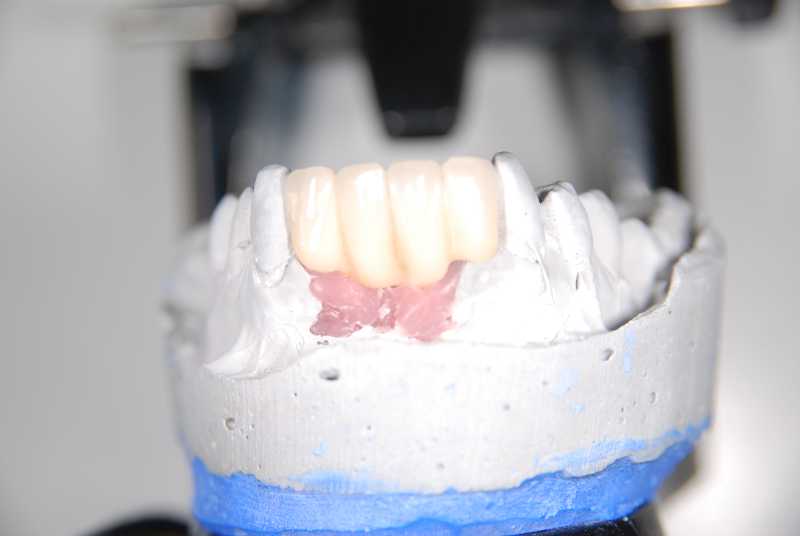

Metal-Porcelain implant bridge on model